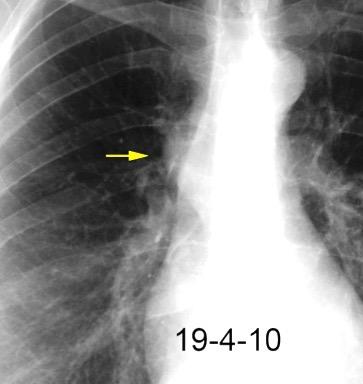

32 años .Preeclampsia a los 19. Hipertensión no controlada. Masa paravertebral sólida que se realza intensamente con afectación ósea.

Yue Y t al. Asymptomatic left posterior mediastinal functional Paraganglioma. A case report. Medicine . 2019